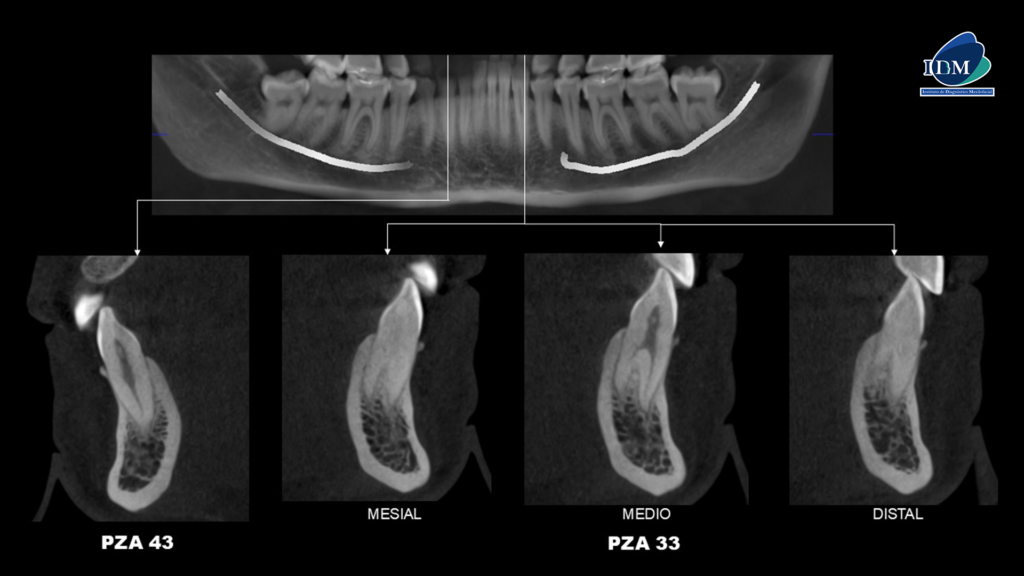

En la radiografía panorámica (Figura 1), se observa pieza 33 con pérdida del lumen del conducto radicular a nivel del tercio medio y apical.

Radiografia Panorámica

A la evaluación de la tomografía volumétrica (cone beam) en los cortes axiales (Figura 2) y transaxiales (Figura 3) se observa la bifurcación del conducto radicular a nivel del tercio medio radicular.

CORTES TRANSAXIALES